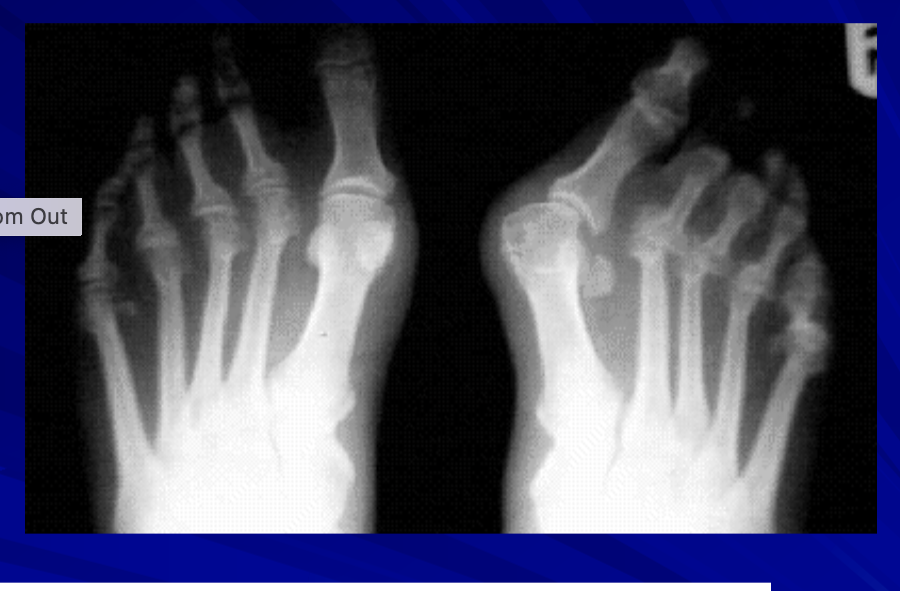

What is “hallux valgus”? MOI?

a deformity where big toe deviates medially than the other phalanges

MOI: genetics, tight shoes, overuse

What is a bunion? MOI?

Excess bony enlargement of the base of big toe

MOI: chronic pressure from tight shoes, genetics

more common in women and passed down by women